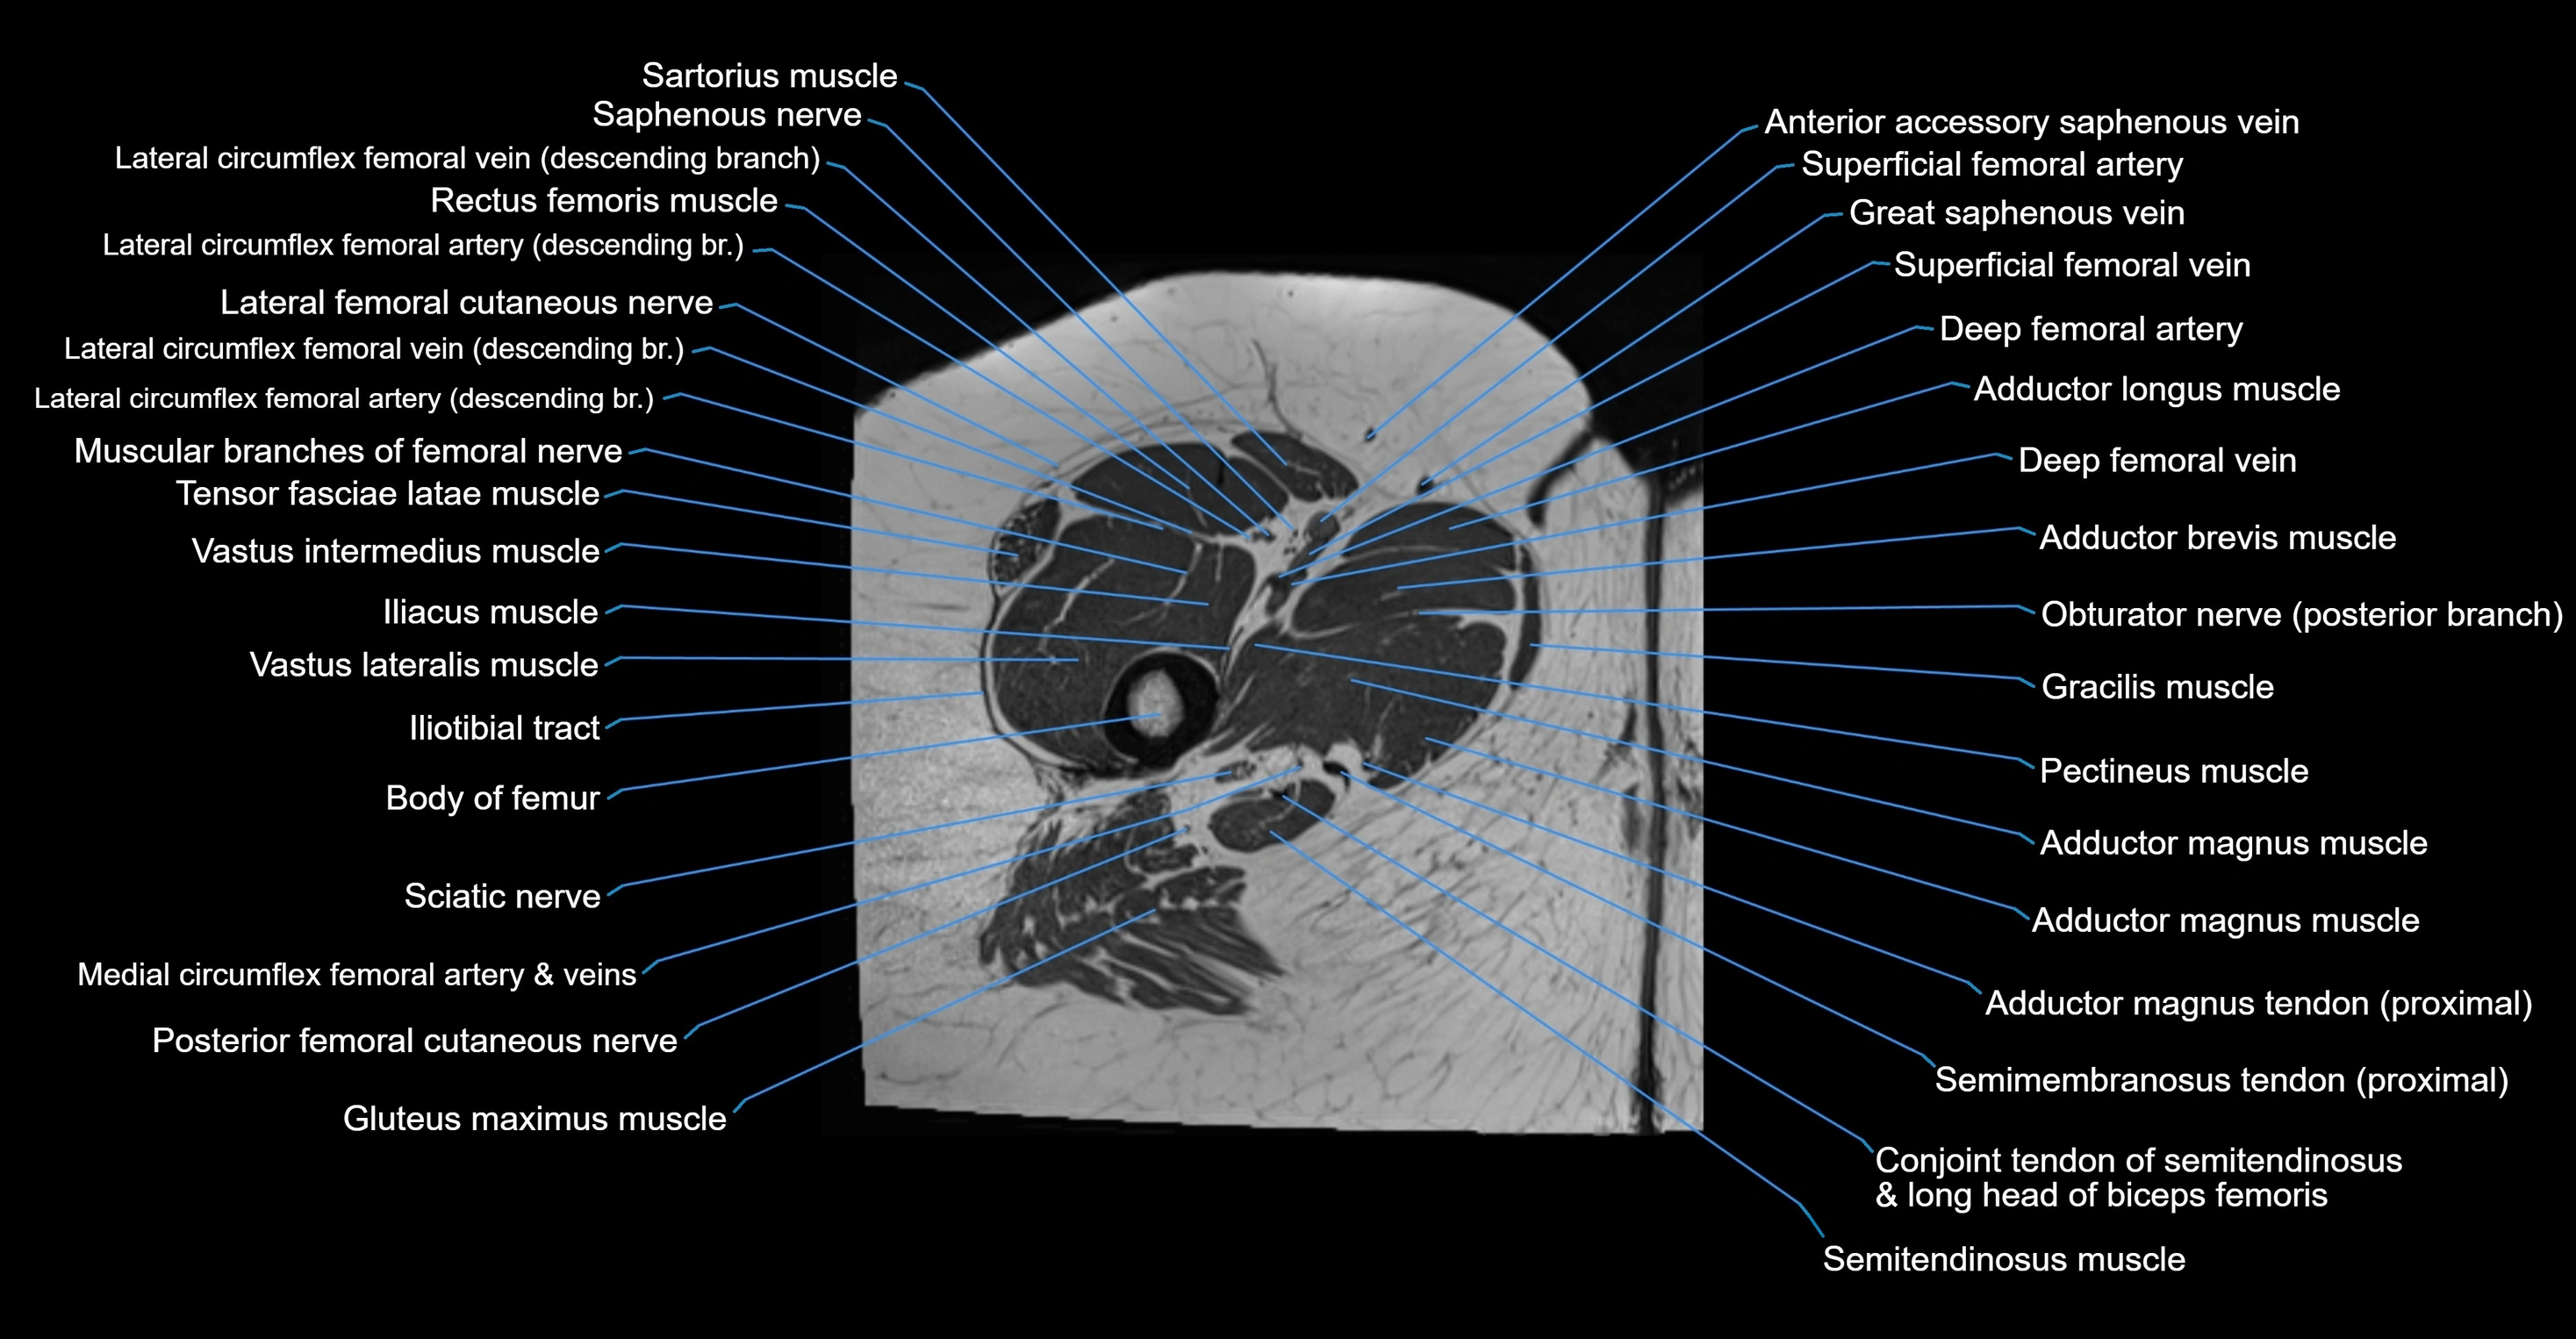

- Body of femur

- Gracilis muscle

- Iliotibial tract

- Muscular branches of femoral nerve

- Pectineus muscle

- Posterior division of obturator nerve (Posterior branch of obturator nerve)

- Posterior femoral cutaneous nerve

- Saphenous nerve

- Sartorius muscle

- Semimembranosus tendon (proximal)

- Tensor fasciae latae muscle

- Vastus intermedius muscle

- Vastus lateralis muscle